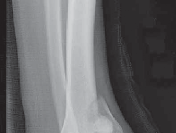

5.

The diagnosis of tibial plafond fracture is initially evaluated with three radiographic views of the ankle (anteroposterior [AP], mortise, and lateral; FIG 4A,B).

CT scans have been clearly shown to improve a surgeon’s understanding of the injury ( FIG 4C) and are critical to preoperative planning for complex injuries.15

7.

For displaced, comminuted pilon fractures, the best time to obtain a CT scan is after temporizing external fixation is performed ( FIG 4D), when the fracture is brought out to length with traction. This tends to grossly reduce many parts of the fracture, making the pathoanatomy of the injury more understandable (FIG 4E,F).

E F ### FIG 4 • 43-C3 tibial plafond injury. A,B. AP and lateral injury radiographs. C. CT scan. D. “Travelling traction”—early ankle-spanning external fixator. E,F. Radiographs of ankle after closed reduction and application of external fixator. G. Three-dimensional reconstruction of CT angiogram demonstrat- G ing deficient flow through anterior tibial artery.